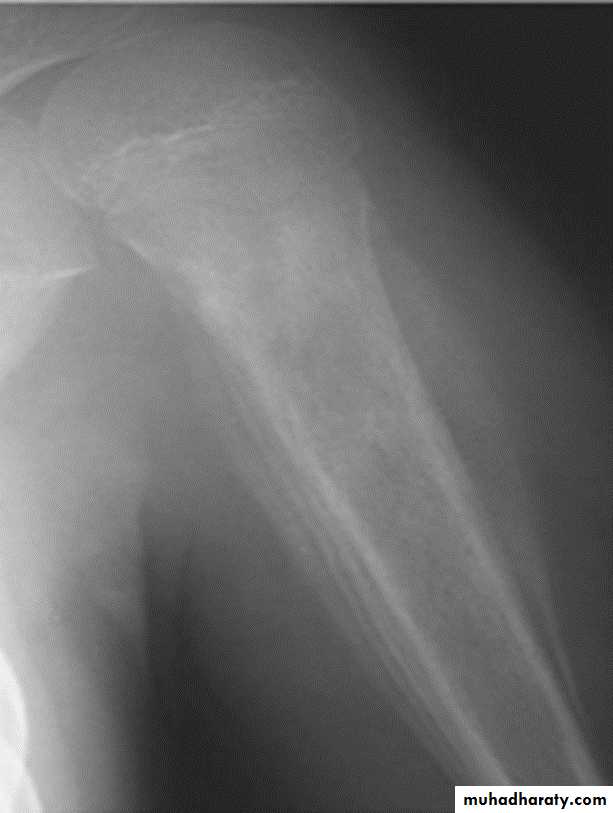

Wide zone of transition is being

Benign or malignant ????Codman's triangle: Elevation of the periosteum at the side of the tumor margin

*Codmans triangle seen in malignant bone tumor (OS)

Codman's triangle is a type of periosteal reaction seen with aggressive bone lesions could be singlelayer and mulitlayered periosteal reaction), only the edge of the raised periosteum will ossify.

* Well defined clear cut with narrow zone of transition indicates benign or slowly growing lesion.* Ill-defined wide zone of transition indicates aggressive rapidly growing lesion as osteo myelitis and malignant tumors.